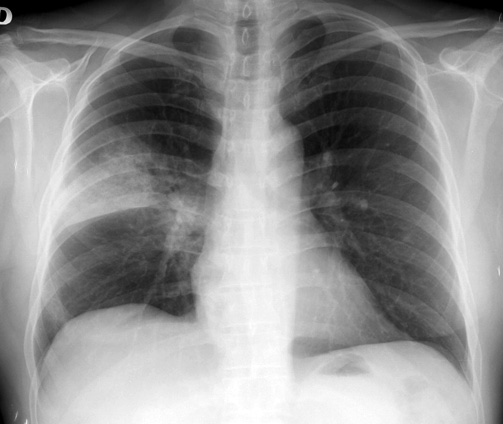

IBP y neumonía adquirida en la comunidad: ¿hay una relación causal?

El uso de los inhibidores de la bomba de protones (IBP) se asocia a un aumento de neumonías en pacientes ambulatorios, pero el riesgo podría explicarse por factores de confusión. BMJ, 15 de noviembre de 2016